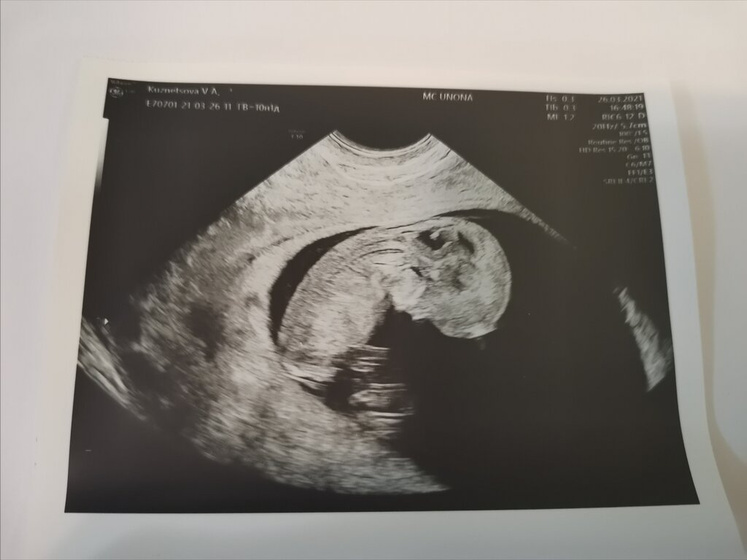

Сходила я сегодня на узи и до безумия счастлива) плавает моя Бубусинка, шевелит ручками и ножками. Все хорошо, развивается хорошо. Очень внимательно узист все посмотрела, я просто счастлива.

Моя Бубусинка уже 40 мм и СБ 174. Поставили срок 10 недель и 6 дней.

Вот это качество узи, все таааак видно хорошо! Лёгкой беременности вам)

Девочки, мне специалист показала все, почки, сердце, желудок, мозг, пальчики и даже ушки) правда сидел и ничего другого посмотреть не получилось)

Я хожу на лучший аппарат в городе и специалисты там очень хорошие)